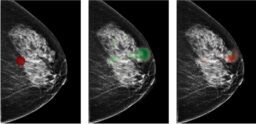

![]() | Utilizing Deep Learning to Mitigate False Positives in Screening MammographyDistilINFO Hospital IT - (Monday April 15, 2024) - Daily Reads / DistilINFO Hospital IT | |||